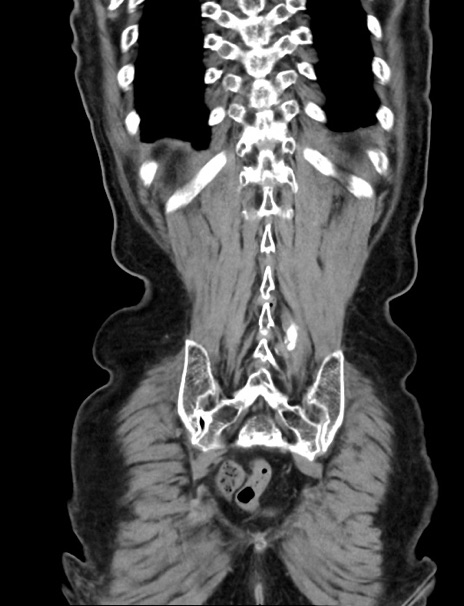

症例33(冠状断像)

【症例】70歳代 女性

【主訴】心窩部痛

【現病歴】延髄病変の精査・加療にて神経内科入院中。本日より心窩部痛あり。

【身体所見】右下腹部を中心に圧痛と反跳痛あり。